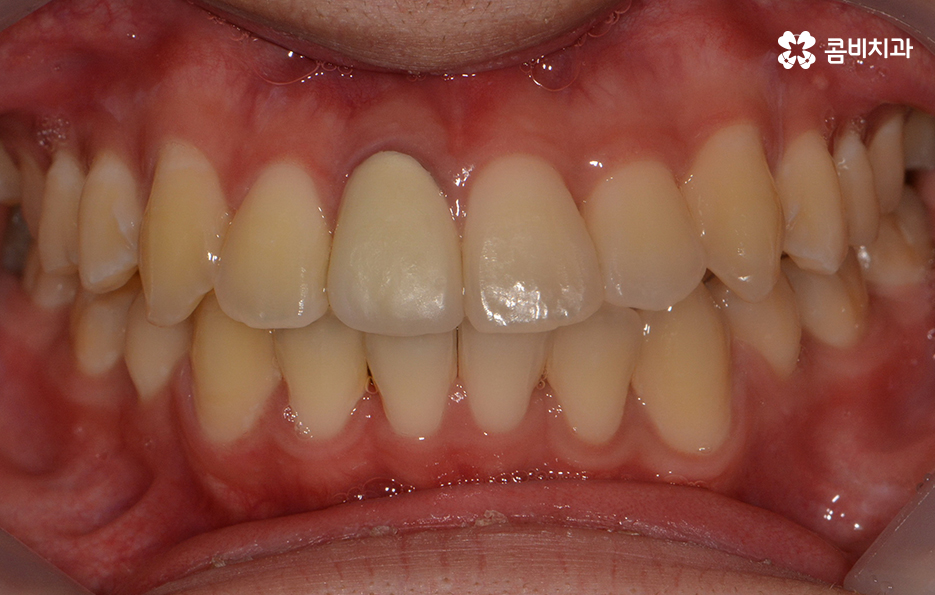

참고로 이번 포스팅에 소개해드린 환자분의 경우

검진부터 발치, 클리피씨 교정을 통해 교정이

마무리 되기 까지 약 2년 정도가 걸렸으며

치료 기간은 개인에 따라 상이하며 정확한 검진 후에

치료 계획에 따라 달라질 수 있어요.